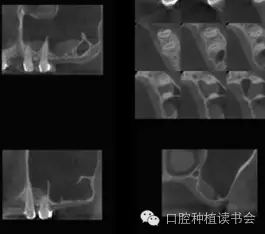

總結(jié)上頜竇腔的骨性結(jié)構(gòu)特點(diǎn),人們發(fā)現(xiàn)上頜竇底并一定是平坦的,有些竇底會有斜坡狀的情況(圖3)。而上頜竇的分隔情況發(fā)生率可達(dá)上頜竇數(shù)量的27.7%,病人數(shù)量的37%。分隔在上頜竇前部占22.5%,中部占45.9%,后部占31.5%(Park,2011)(圖4)。所以SFE的障礙之一就是骨性結(jié)構(gòu)的變異,給提升技術(shù)和工具帶來挑戰(zhàn)。

▲(圖3)

▲(圖4)